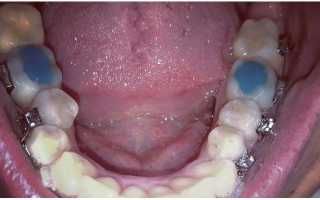

Надкусочные пломбы при брекетах – это временная установка, которая регулирует соприкосновение жевательных зубов между собой и с выравнивающими конструкциями. Визуально они похожи на обычные пломбы, но иногда изготавливаются из цветного материала.

Название «надкусочные пломбы» имеет естественное происхождение, поскольку они нужны именно для надкусывания. Временная конструкция позволяет регулировать процесс коррекции положения зуба и помогает в исправлении анатомических дефектов челюсти.

Временные накладки на зубы необходимы для того, чтобы контролировать и корректировать момент соприкосновения моляров. На передние зубы они не устанавливаются.

image Чтобы предотвратить такие проблемы, стоматологи устанавливают пациенту на жевательные зубы защиту. Временные устройства необходимы, чтобы:

• обеспечить правильное соприкосновение зубов;

• предотвратить повреждение эмали;

• избежать случайного отклеивания брекета;

• восстановить правильную жевательную функцию;

• сократить период использования брекетов;

• увеличить высоту прикуса в нужных местах;

• нормализовать нагрузку на челюстные суставы и мышцы.